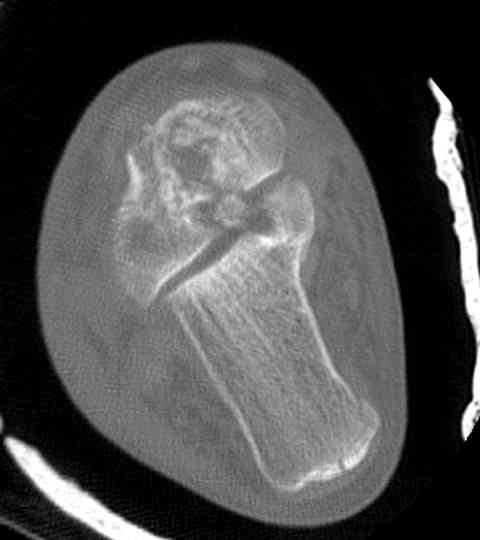

Случай с множественным оскольчатым переломом тарана оперированный из двойного доступа.

Через 2 мес.: